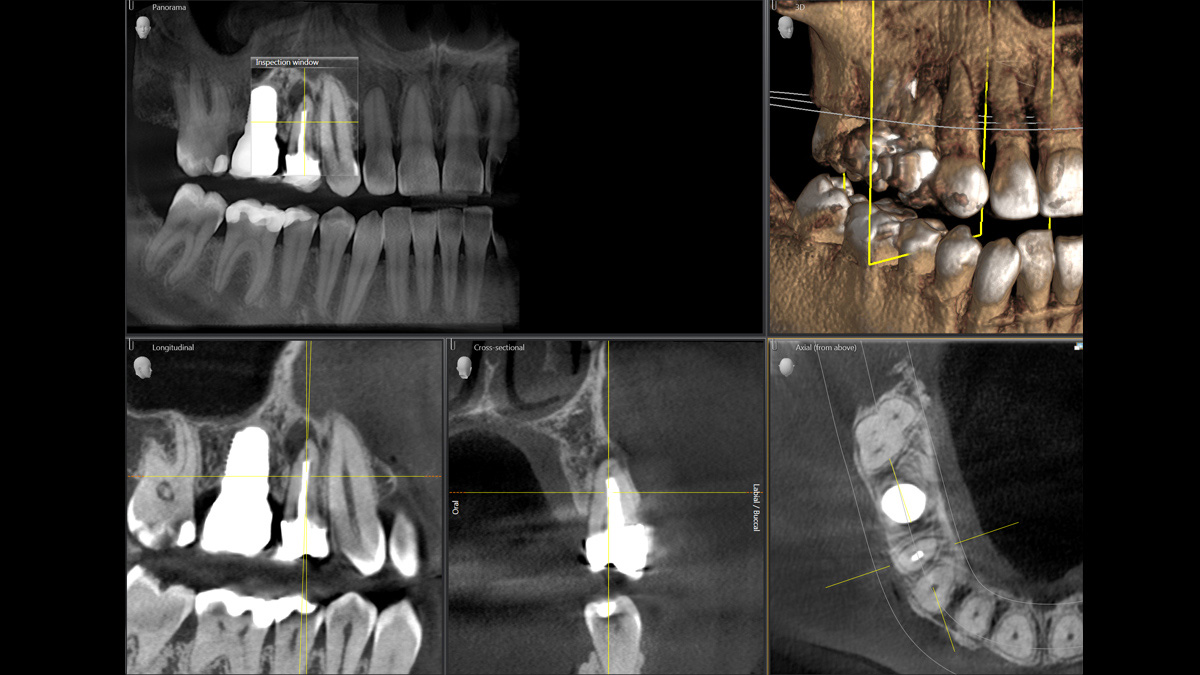

With the 3D Intelligent Low Dose mode, you get 3D images in the dose range of a 2D X-ray. In HD mode (up to 1,400) individual images are captured during a single rotation and converted into a 3D volume with up to 80 μm for low-noise images in high resolution.

A broad range of volume sizes to support your various diagnostic and clinical needs from Ø 5 x 5.5 cm to Ø 11 x 10 cm